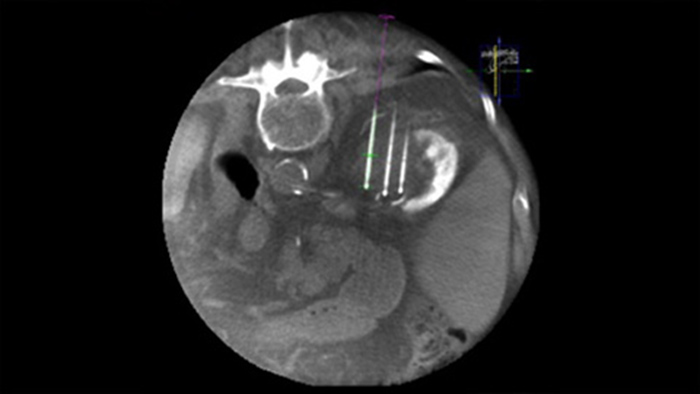

La ablación percutánea (radiofrecuencia, microondas y crioablación) es un tratamiento mínimamente invasivo bien establecido para los tumores de riñón, hígado, pulmón y hueso. Es fundamental definir los límites del tumor y decidir el número óptimo de agujas y la correspondiente trayectoria de estas para poder realizar un tratamiento completo del tumor y no causar daños en el tejido circundante. Navegar con precisión con baja dosis hasta la lesión de interés sin reposicionar la aguja aumenta las posibilidades de éxito y reduce el riesgo de complicaciones de las biopsias o ablaciones. La confirmación del punto final del tratamiento de ablación puede realizarse con imágenes en 3D mientras el paciente sigue en la mesa.

Dual View permite la superposición de una imagen 3D previa al procedimiento (TC/RM/TEP) sobre una THC Dual 3D intraprocedimiento para visualizar mejor las lesiones y acceder a información crítica para la planificación de la trayectoria de la aguja.